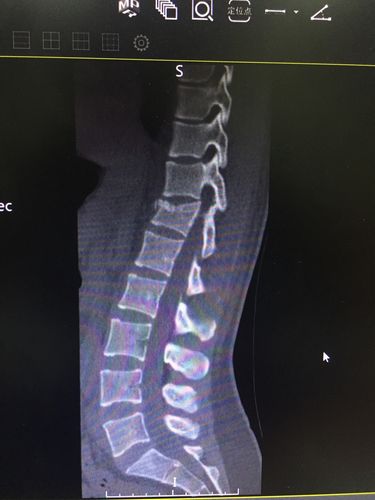

ct示:t12椎体压缩性粉碎性骨折并骨性椎管狭窄严重.

t12椎体压缩性骨折(田欢)